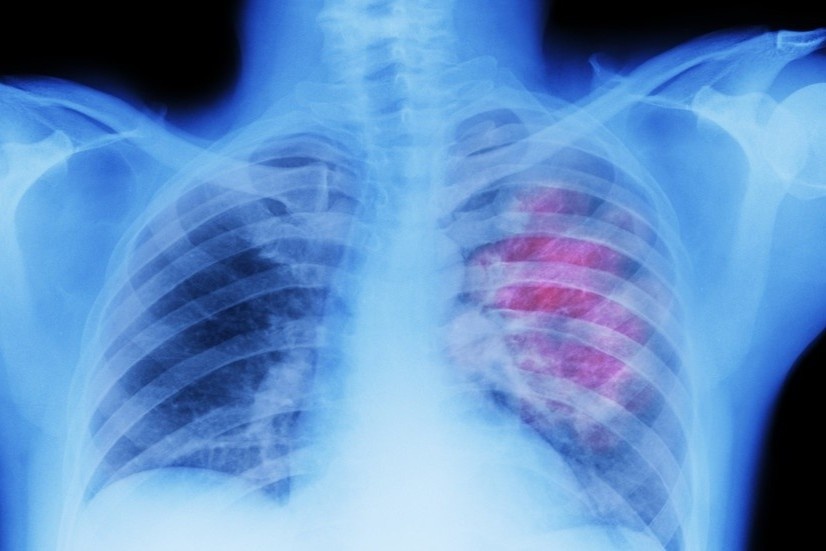

Nghiên cứu của Italy phát hiện phụ nữ dễ bị khó thở, suy nhược, đau ngực và rối loạn giấc ngủ hơn so với nam giới trong giai đoạn hồi phục hậu Covid-19.

Các chuyên gia nhận định tình trạng tổn thương phổi của bệnh nhân này rất nặng, tương tự nam phi công người Anh.

Nghiên cứu của nhóm nhà khoa học Anh chỉ ra 0,91% bệnh nhân bị thủng phổi nặng do Covid-19 và nam giới có nguy cơ cao gấp 3 lần phụ nữ.